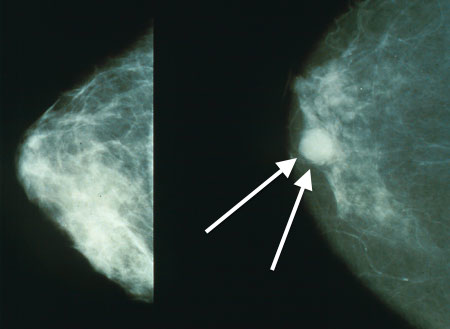

In this notebook, we will analyze a skewed dataset for detecting microcalcifications in mammograms. The goal is to build a classifier to identify whether a bright spot in a mammogram is a micro-calcification (an early sign of breast cancer).

Figure 1:Micro-calcification